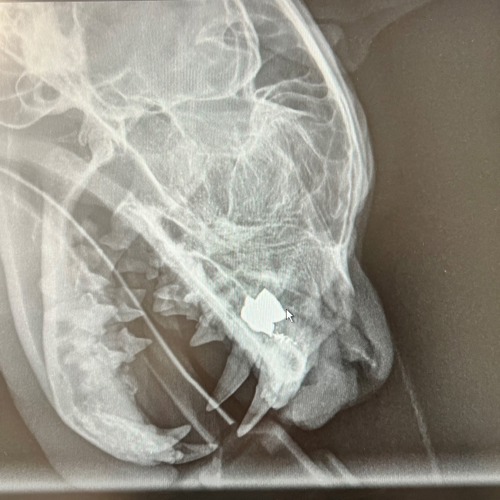

Leo's x-ray showing the air gun pellet

There was shock all round when the root of the problem was revealed to be an air gun pellet. With no visible entry wound, it was determined poor Leo must have been shot some time ago.

“The x-rays were really quite shocking and an initial non-surgical attempt to remove it was unsuccessful as there was too much inflammation.